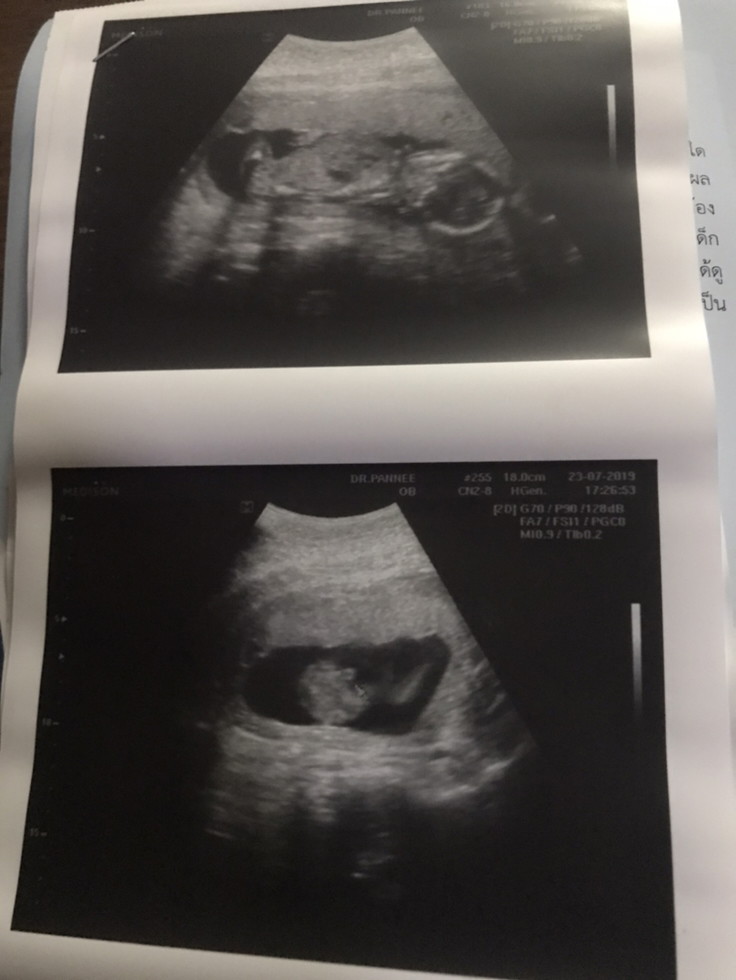

ตอน 18 w จ้า หันหน้าหากล้อง 555 ตอนนี้ 20 w แล้วค่ะ ครึ่งทางแล้ว 😂😂

ตอนไปซาวด์มาหันหน้าออกนอกท้องแบบนี้เหมือนกันคะ อิอิ

ผู้ชายคะ น้องหันหน้ามาพอดีเลย 25. ธ.ค. เหมือนกันจร้า